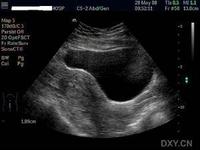

异位妊娠

3、基层单位有条件先行补液,紧急转院处理。异位妊娠宫外孕的防治:注意经期、产期和产褥期的卫生,防止生殖系统的感染。如果已经发病应该及时去医院输液、输血,同时立即做剖腹探察手术。宫外孕是产科较常见且严重的病症,如诊断处理不及时,可危及生命。输卵管妊娠最常见的原因是慢性输卵管炎,炎症使输卵管变形,狭窄、蠕动能力差,甚至阻塞,使受精卵运行受阻。其次是输卵管发育不良,输卵管细而长,蠕动能力弱,使受精卵运行缓慢,不能及时到达子宫腔而种植在输卵管内。由于输卵管壁薄,管腔狭小,受精卵种植后,绒毛像小树根样长人输卵管肌壁,破坏肌层内血管引起出血,特别是当大血管破裂时,可引起大出血,血液流人腹腔,引起腹痛和休克,因此比较危险。